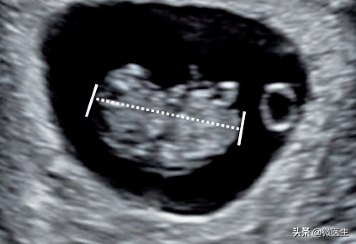

(5)头臀长检査及测量全面扫査妊娠囊,观察胚胎及数目,胚胎最大长轴切面或在胎儿正中矢状切面测量头臀长,胎儿自然伸展姿势。

孕8周,经腔内超声检查,胎芽长2.6cm